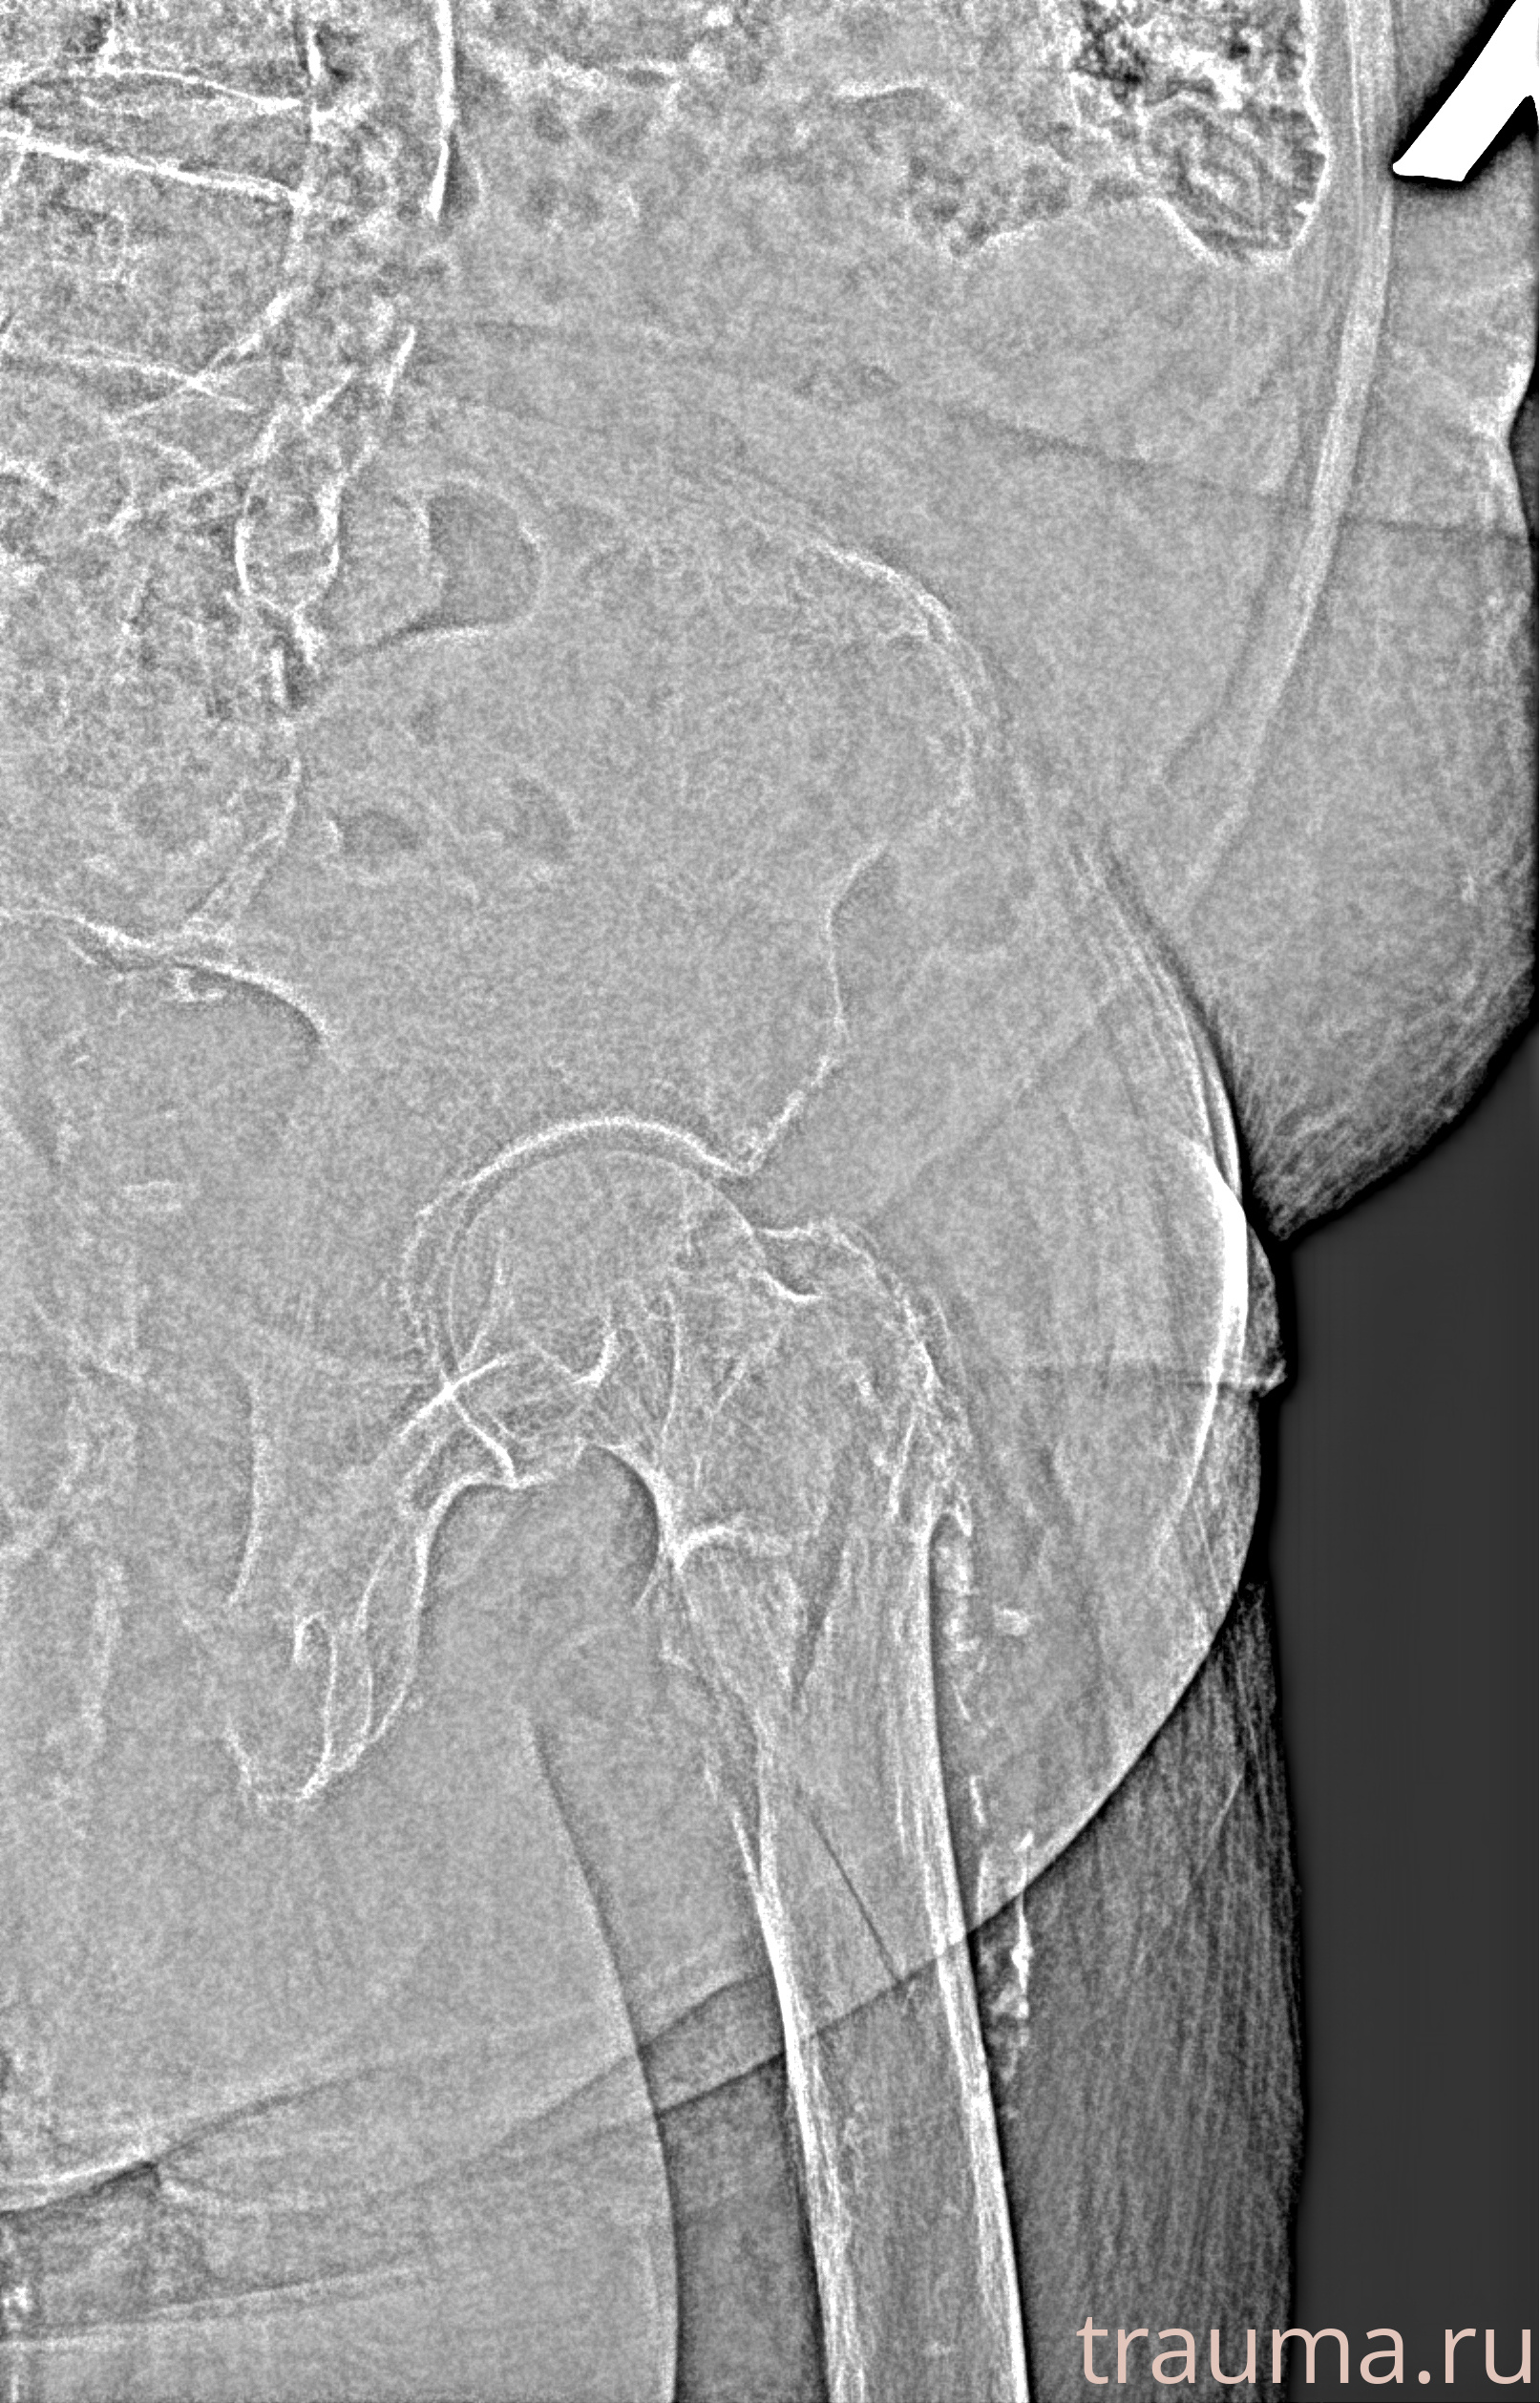

Рентгенограммы

Рентген на дому: по вашему адресу приезжает врач-рентгенолог, травматолог-ортопед с мобильным рентгеновским аппаратом, проводит диагностику травмы или заболевания, делает необходимые рентгенограммы, дает рекомендации по дальнейшему лечению. Получить качественные снимки в домашних условиях возможно благодаря уникальной методике, разработанной МосРентген Центром для института  Склифосовского

Яркость: 1   Контраст: 1   Инвертировать: 0 Увеличение: 1

Перетаскивайте мышь вверх/вниз для контраста, влево/право для яркости. Прокрутка колесом изменяет масштаб. Нажмите Сбросить для возврата к исходному изображению. При увеличении держите мышь в той области, которую хотите рассмотреть.